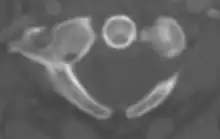

The atlas's chief peculiarity is that it has no body,[3] which has fused with the next vertebra.[4] It is ring-like and consists of an anterior and a posterior arch and two lateral masses.

Vertebral foramen

Just below the medial margin of each superior facet is a small tubercle, for the attachment of the transverse atlantal ligament which stretches across the ring of the atlas and divides the vertebral foramen into two unequal parts:

- the anterior or smaller receiving the odontoid process of the axis

- the posterior transmitting the spinal cord (medulla spinalis) and its membranes

This part of the vertebral canal is of considerable size, much greater than is required for the accommodation of the spinal cord.